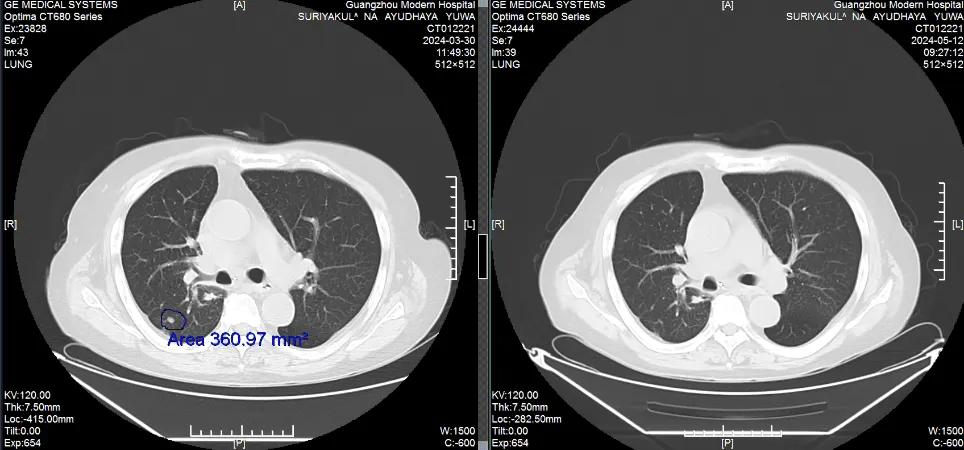

Сравнение КТ лёгких до и после лечения. Опухоль лёгких практически инактивирована

(Слева: до лечения, справа: после лечения)

Лечение дало ошеломляющие результаты: • После двух процедур КТ показало уменьшение очага в легком, а колоноскопия - значительное сокращение опухоли в кишечнике. • Исчезли мучительные симптомы: кашель и кровавый стул. • После семи сеансов опухоль в легком была практически полностью инактивирована, а в кишечнике - уменьшилась на 90%. Путь не был усыпан розами. Однажды у Радика резко упал уровень тромбоцитов, что грозило опасным кровотечением. В момент отчаяния именно настойчивость и профессионализм его лечащего врача, доктора Аденана, и всей команды спасли ситуацию. Быстро проведенная симптоматическая терапия стабилизировала состояние, и лечение было продолжено.